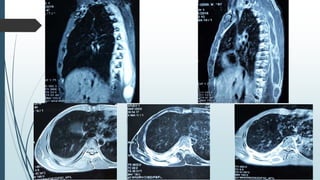

MRI

T1WI – Iso to hypointense

T2WI – hyperintense

Post contrast – rim enhancing

MRI T1WI – Isoto hypointense T2WI – hyperintense Post contrast – rim enhancing